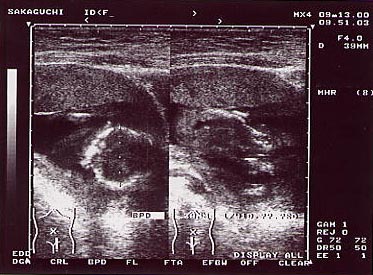

◆写真◆

ベイビーのエコー写真です。

今日、はじめてベイビーの心音を聞かせてもらいました。大人の倍の速さで蒸気機関車のような音だったよ。相変らず、私のベイビーはちっともじっとしてくれなくて、ナイスショットな写真が撮れません。もうだいぶ大きくなったんで、1枚の写真に全体が写らなくなってしまいました。

パパに似て、手足が長いです。どうかこのままで生まれてくれ! ベイビーちゃんったら、約2週間くらい成長が早いんで、先生がびっくりしてます。とにかくすくすく育ってます。